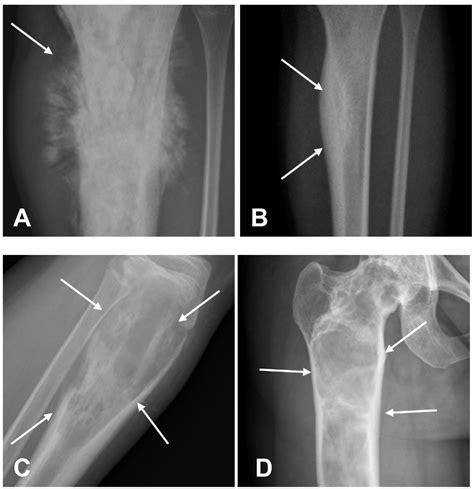

Imaging tests, such as X-rays, CT scans, and MRIs, can help identify the location and extent of the cancer. These tests can also provide information about the bone structure and any potential fractures or deformities. However, imaging tests alone are not sufficient for a definitive diagnosis.

A biopsy is essential for confirming the presence of cancer cells and determining the type of cancer. During a biopsy, a small sample of tissue is removed from the affected area and examined under a microscope. The biopsy can help distinguish between *Ewing Sarcoma vs Osteosarcoma* based on the type of cells involved and the presence of specific genetic mutations.